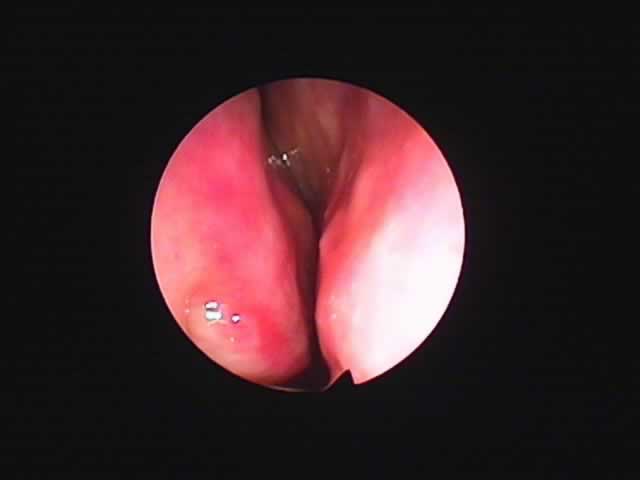

| 左扁桃術直後(31歳男性,6月9日) 数カ所針電極を刺入 | 白い部分が変性部位(6月11日) | 右扁桃術直後(7月7日) |

![]() |